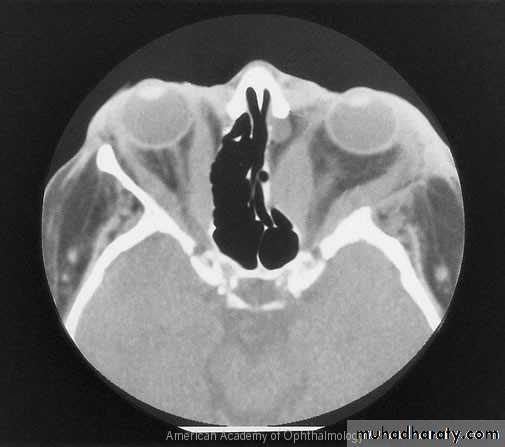

X-rayC.T. scan

Proptosis

Abnormal communication between internal carotid artery and cavernous sinusCauses; rupture congenital aneurysm or post traumatic

Clinical features;Congested vessels,

Chemosis,

Hyperemic disc,

Pulsating exophthalmus